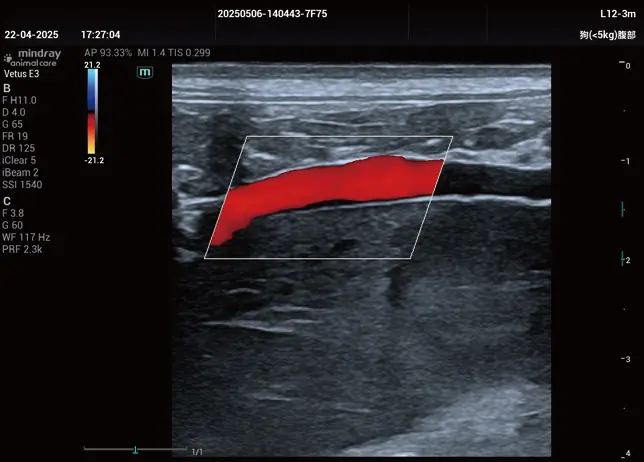

Mikrovasküler veya karmaşık akım paternlerinin görselleştirilmesini geliştiren yenilikçi bir teknolojidir. Mindray Animal’a özgü gelişmiş görüntü işleme algoritmalarıyla, akımın detaylı olarak izlenmesine olanak tanır. HR Flow, hem Renkli Doppler hem de Power Doppler modlarında uygulanabilir.

Tek dokunuşla vasküler yapı görüntülemesinde hızlı ve akıllı optimizasyon sağlar. Smart Track, Renkli, Power Doppler ve PW spektrum modlarında otomatik izleme yaparak zaman alan manuel ayarları ortadan kaldırır.